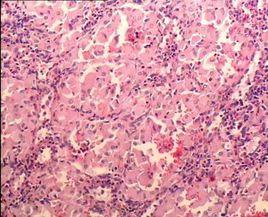

骨髓形態學檢查

大多數戈謝病患者骨髓形態學檢查能發現特徵性細胞即“戈謝細胞”,該細胞體積,細胞核小,部份胞質可見空泡。但該檢查存在假陰性及假陽性的情況。 假陰性: 即當未查見戈謝細胞時,仍不能否定患有戈謝病,需要通過葡萄糖腦苷脂酶活性檢測進行確診。假陽性:骨髓中的單核巨噬細胞等會吞噬細胞碎片或脂質代謝產物,形成與“戈謝細胞”相似的“類戈謝細胞”,在慢性髓性白血病、地中海貧血、多發性骨髓瘤、霍奇金淋巴瘤、漿細胞樣淋巴瘤中都可能出現這種“類戈謝細胞”。因此,當骨髓中查見“戈謝細胞”時, 應高度懷疑戈謝病,但並不能確診戈謝病,需在鑑別區分其他疾病的同時,進一步做葡萄糖腦苷脂酶活性測定 。